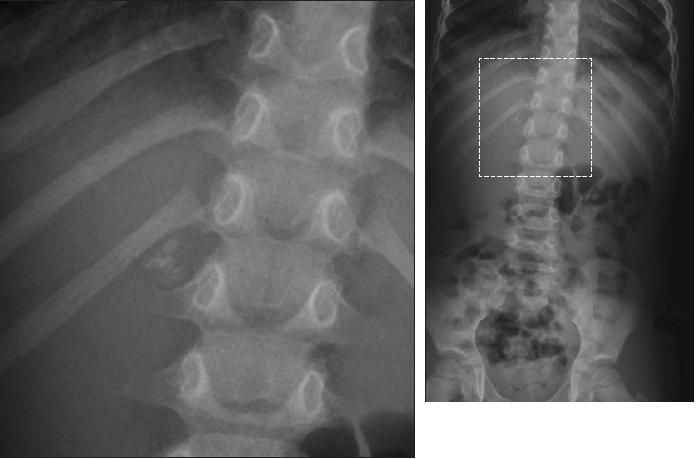

Here the workup gets a little murky. Because the patient had right upper quadrant pain and trace hematuria, ultrasonography of the kidneys was performed in hopes that it would demonstrate the calcifications in a small adrenal gland or in the kidney-or perhaps in the gallbladder. Nephrolithiasis was thought to be less likely based on the radiographs, which demonstrate a fairly classic appearance for adrenal calcifications-an incidental finding probably resulting from a remote insult (such as a hemorrhage). However, the sonograms eliminated cholelithiasis and nephrolithiasis as possible causes of her symptoms, and we were still unable to locate the calcifications.

At this point, limited unenhanced CT of the upper abdomen was performed to characterize the calcifications once and for all.

What are the findings in the upper abdomen? (D is the correct choice.)

Whether the CT scan was absolutely necessary in this patient's case is open to debate; however, this is in fact how the saga unfolded. Indeed, in the right suprarenal fossa are dystrophic, benign-appearing calcifications scattered throughout the right adrenal gland, which is of normal contour and size. There were no renal or liver calcifications, nor were there any rib fractures. It would be unwise to rely on a CT scan to show gallstones, if they were present. CT is notoriously misleading in this regard. Because gallstones vary in composition and density, they may be present but completely inapparent on CT scans. However, we had already eliminated this possibility on the sonogram.